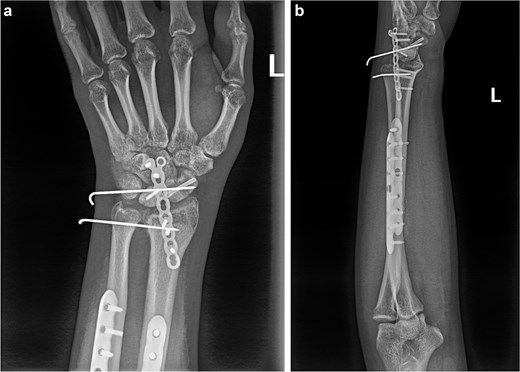

(a and b) Anterior and lateral views of the wrist joint following the second postoperative intervention, demonstrated satisfactory reduction of the fracture ends of the wrist bones, and the lunate bone had been relocated.

(a and b) Anterior and lateral views of the wrist joint after 6-month follow-up.